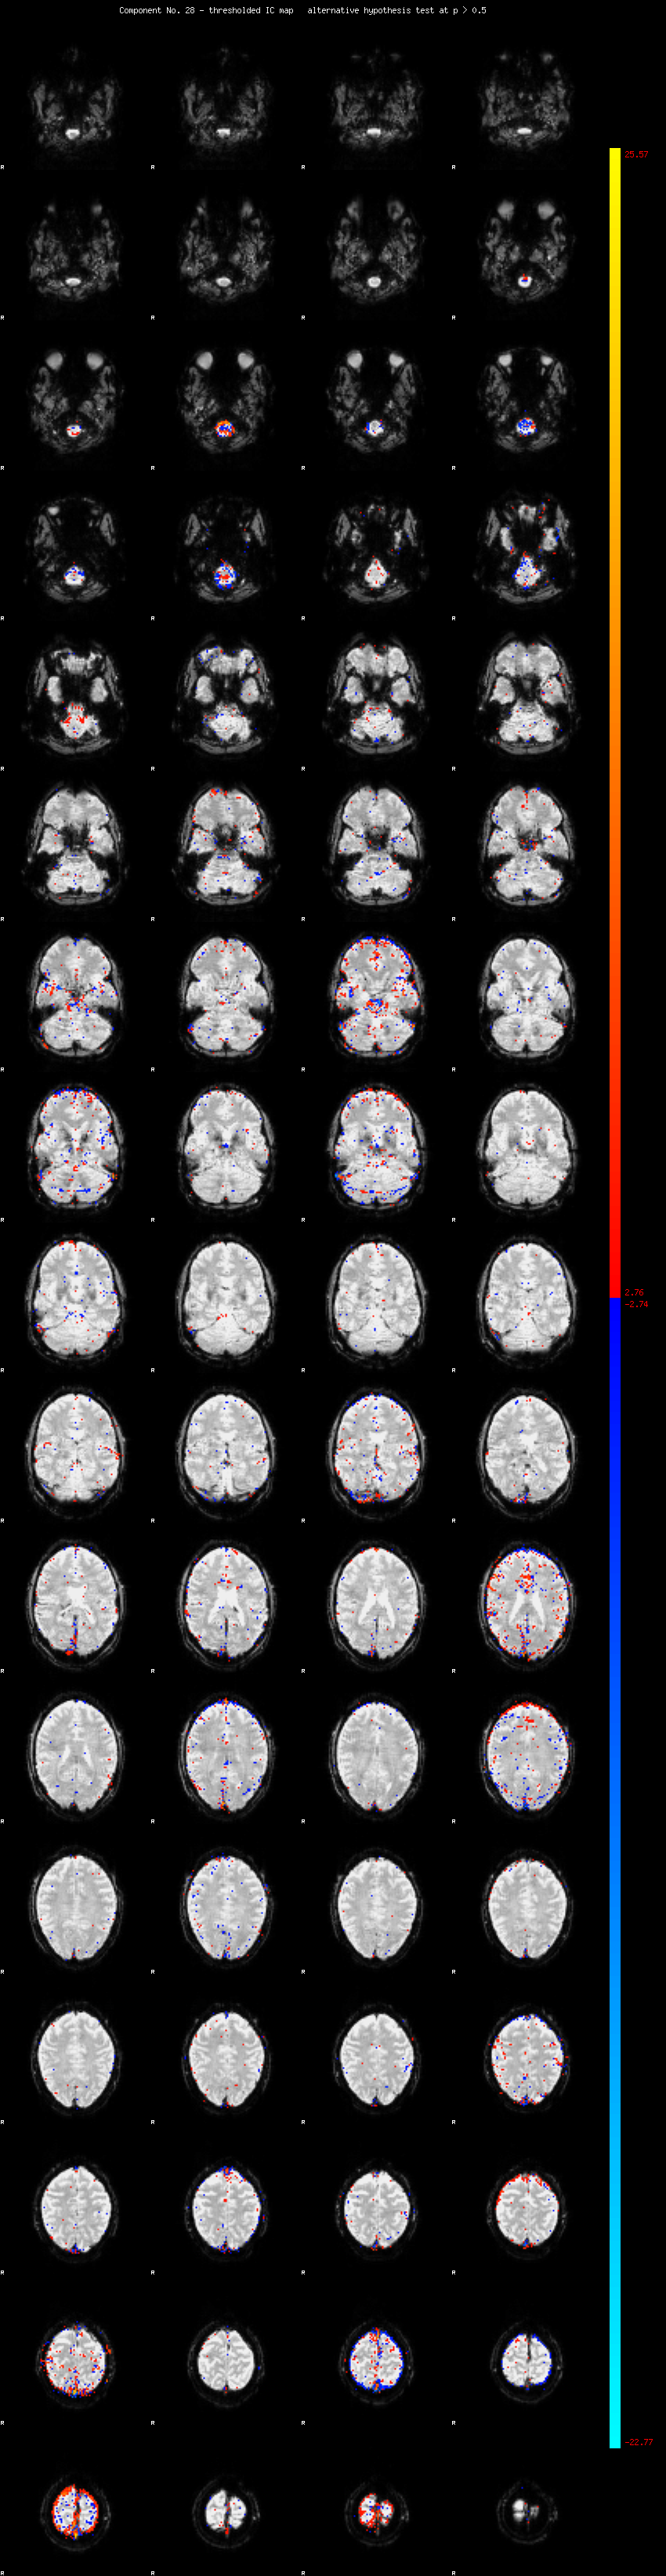

MELODIC Component 28

1.25 % of explained variance;     0.83 % of total variance

MMfit